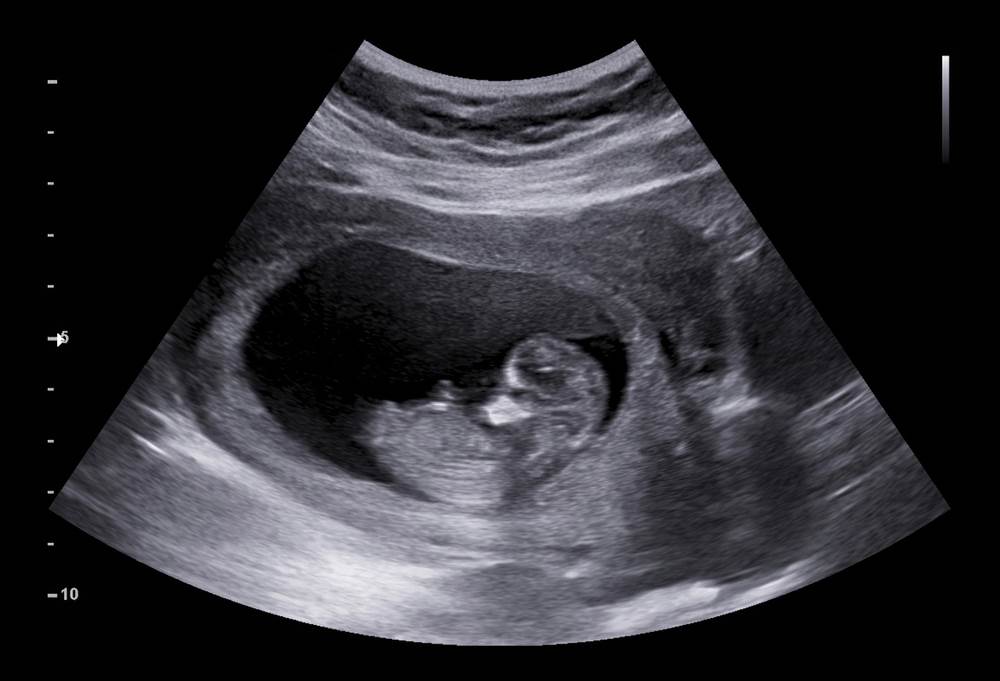

Prema Anne Brown, dr. med., medicinskoj direktorici službe za zdravlje žena u bolnici Inova Loudoun u Virginiji, "početak trećeg tromjesečja je kada većina žena počinje osjećati fetalno štucanje, ali na ultrazvuku se vidi već u prvom tromjesečju, kada se razvija bebina dijafragma."